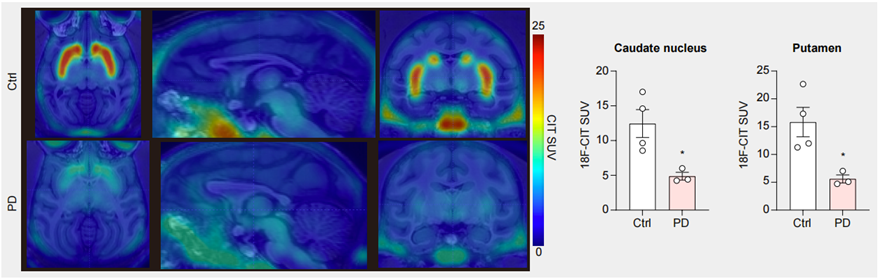

图3. PET-CT结果显示PD模型猴脑中多巴胺神经元减少